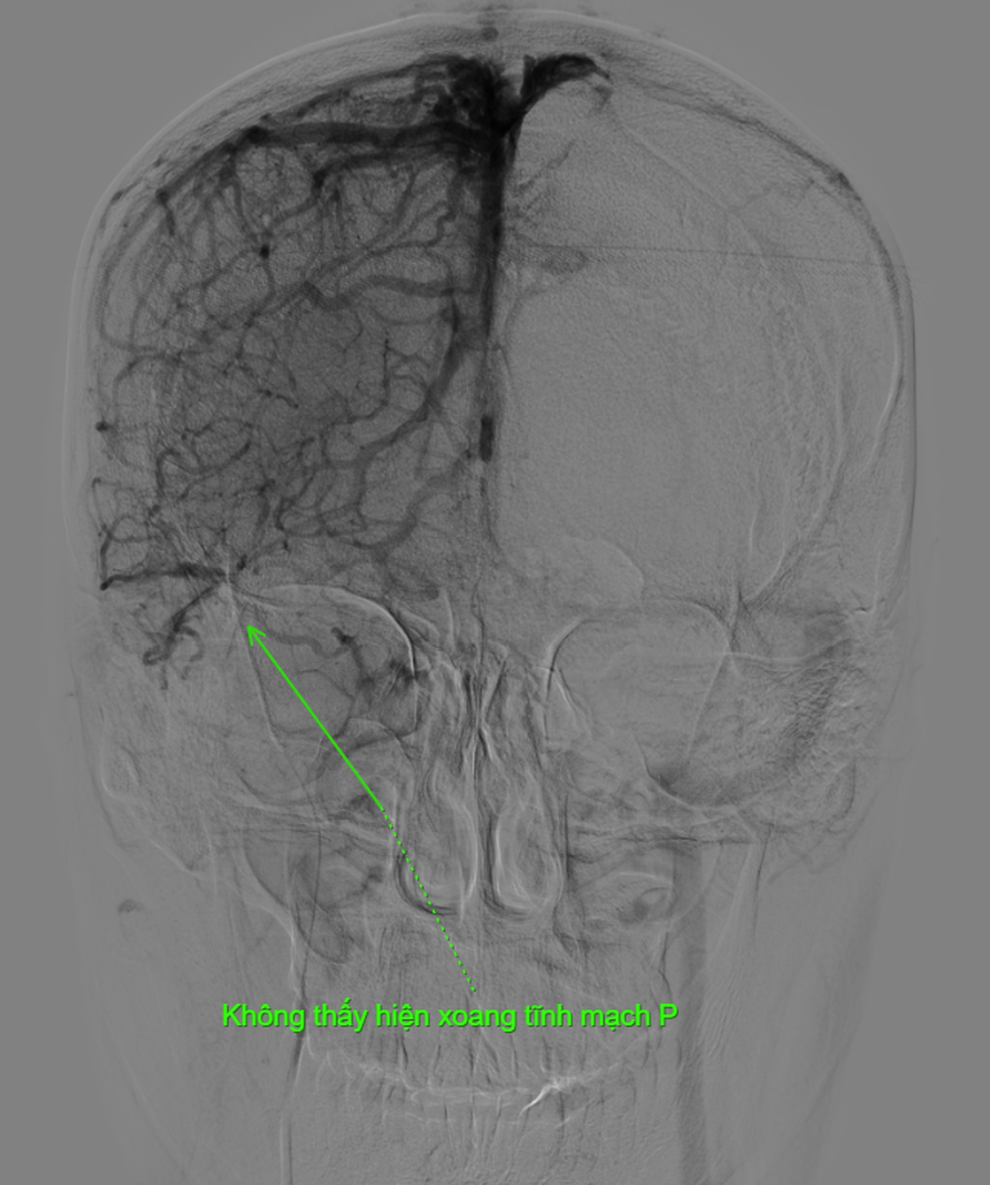

Kết quả phim chụp tại Bệnh viện Việt Đức cho thấy bệnh nhân bị tắc gần như toàn bộ hệ thống tĩnh mạch dẫn lưu não, bao gồm xoang dọc trên, xoang ngang, xoang sigma và đoạn đầu xoang tĩnh mạch cảnh trong phải.

Hình ảnh phim chụp cho thấy rõ mức độ tắc nghẽn nghiêm trọng của người bệnh (Ảnh: Bệnh viện cung cấp).

Bác sĩ Đào Xuân Hải – Khoa Chẩn đoán hình ảnh, Bệnh viện Việt Đức cho biết, đa số bệnh nhân huyết khối tĩnh mạch não đáp ứng tốt với điều trị nội khoa nhưng trường hợp này huyết khối rất lớn, tắc hoàn toàn các xoang tĩnh mạch lớn và diễn tiến xấu đi dù đã dùng thuốc.